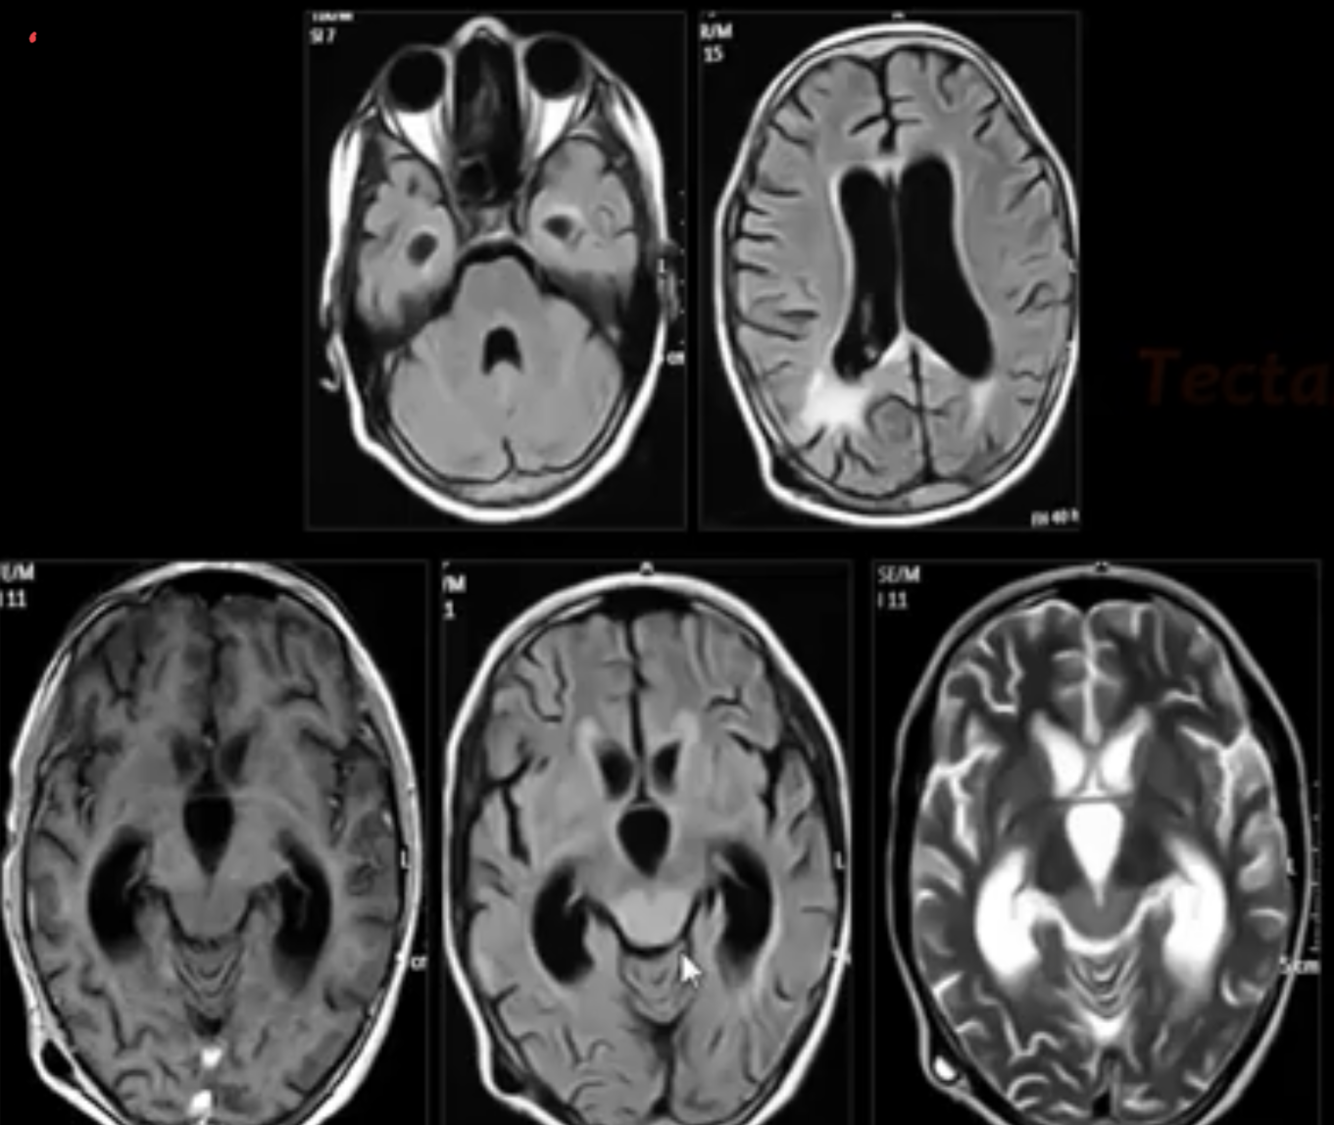

TECTAL GLIOMAS

major points